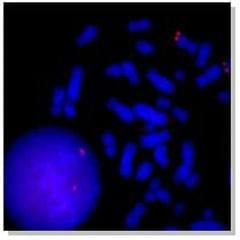

Próbki sond FISH:

Sygnał hybrydyzacji ludzkiej sondy genowej XIST ( czerwony) |